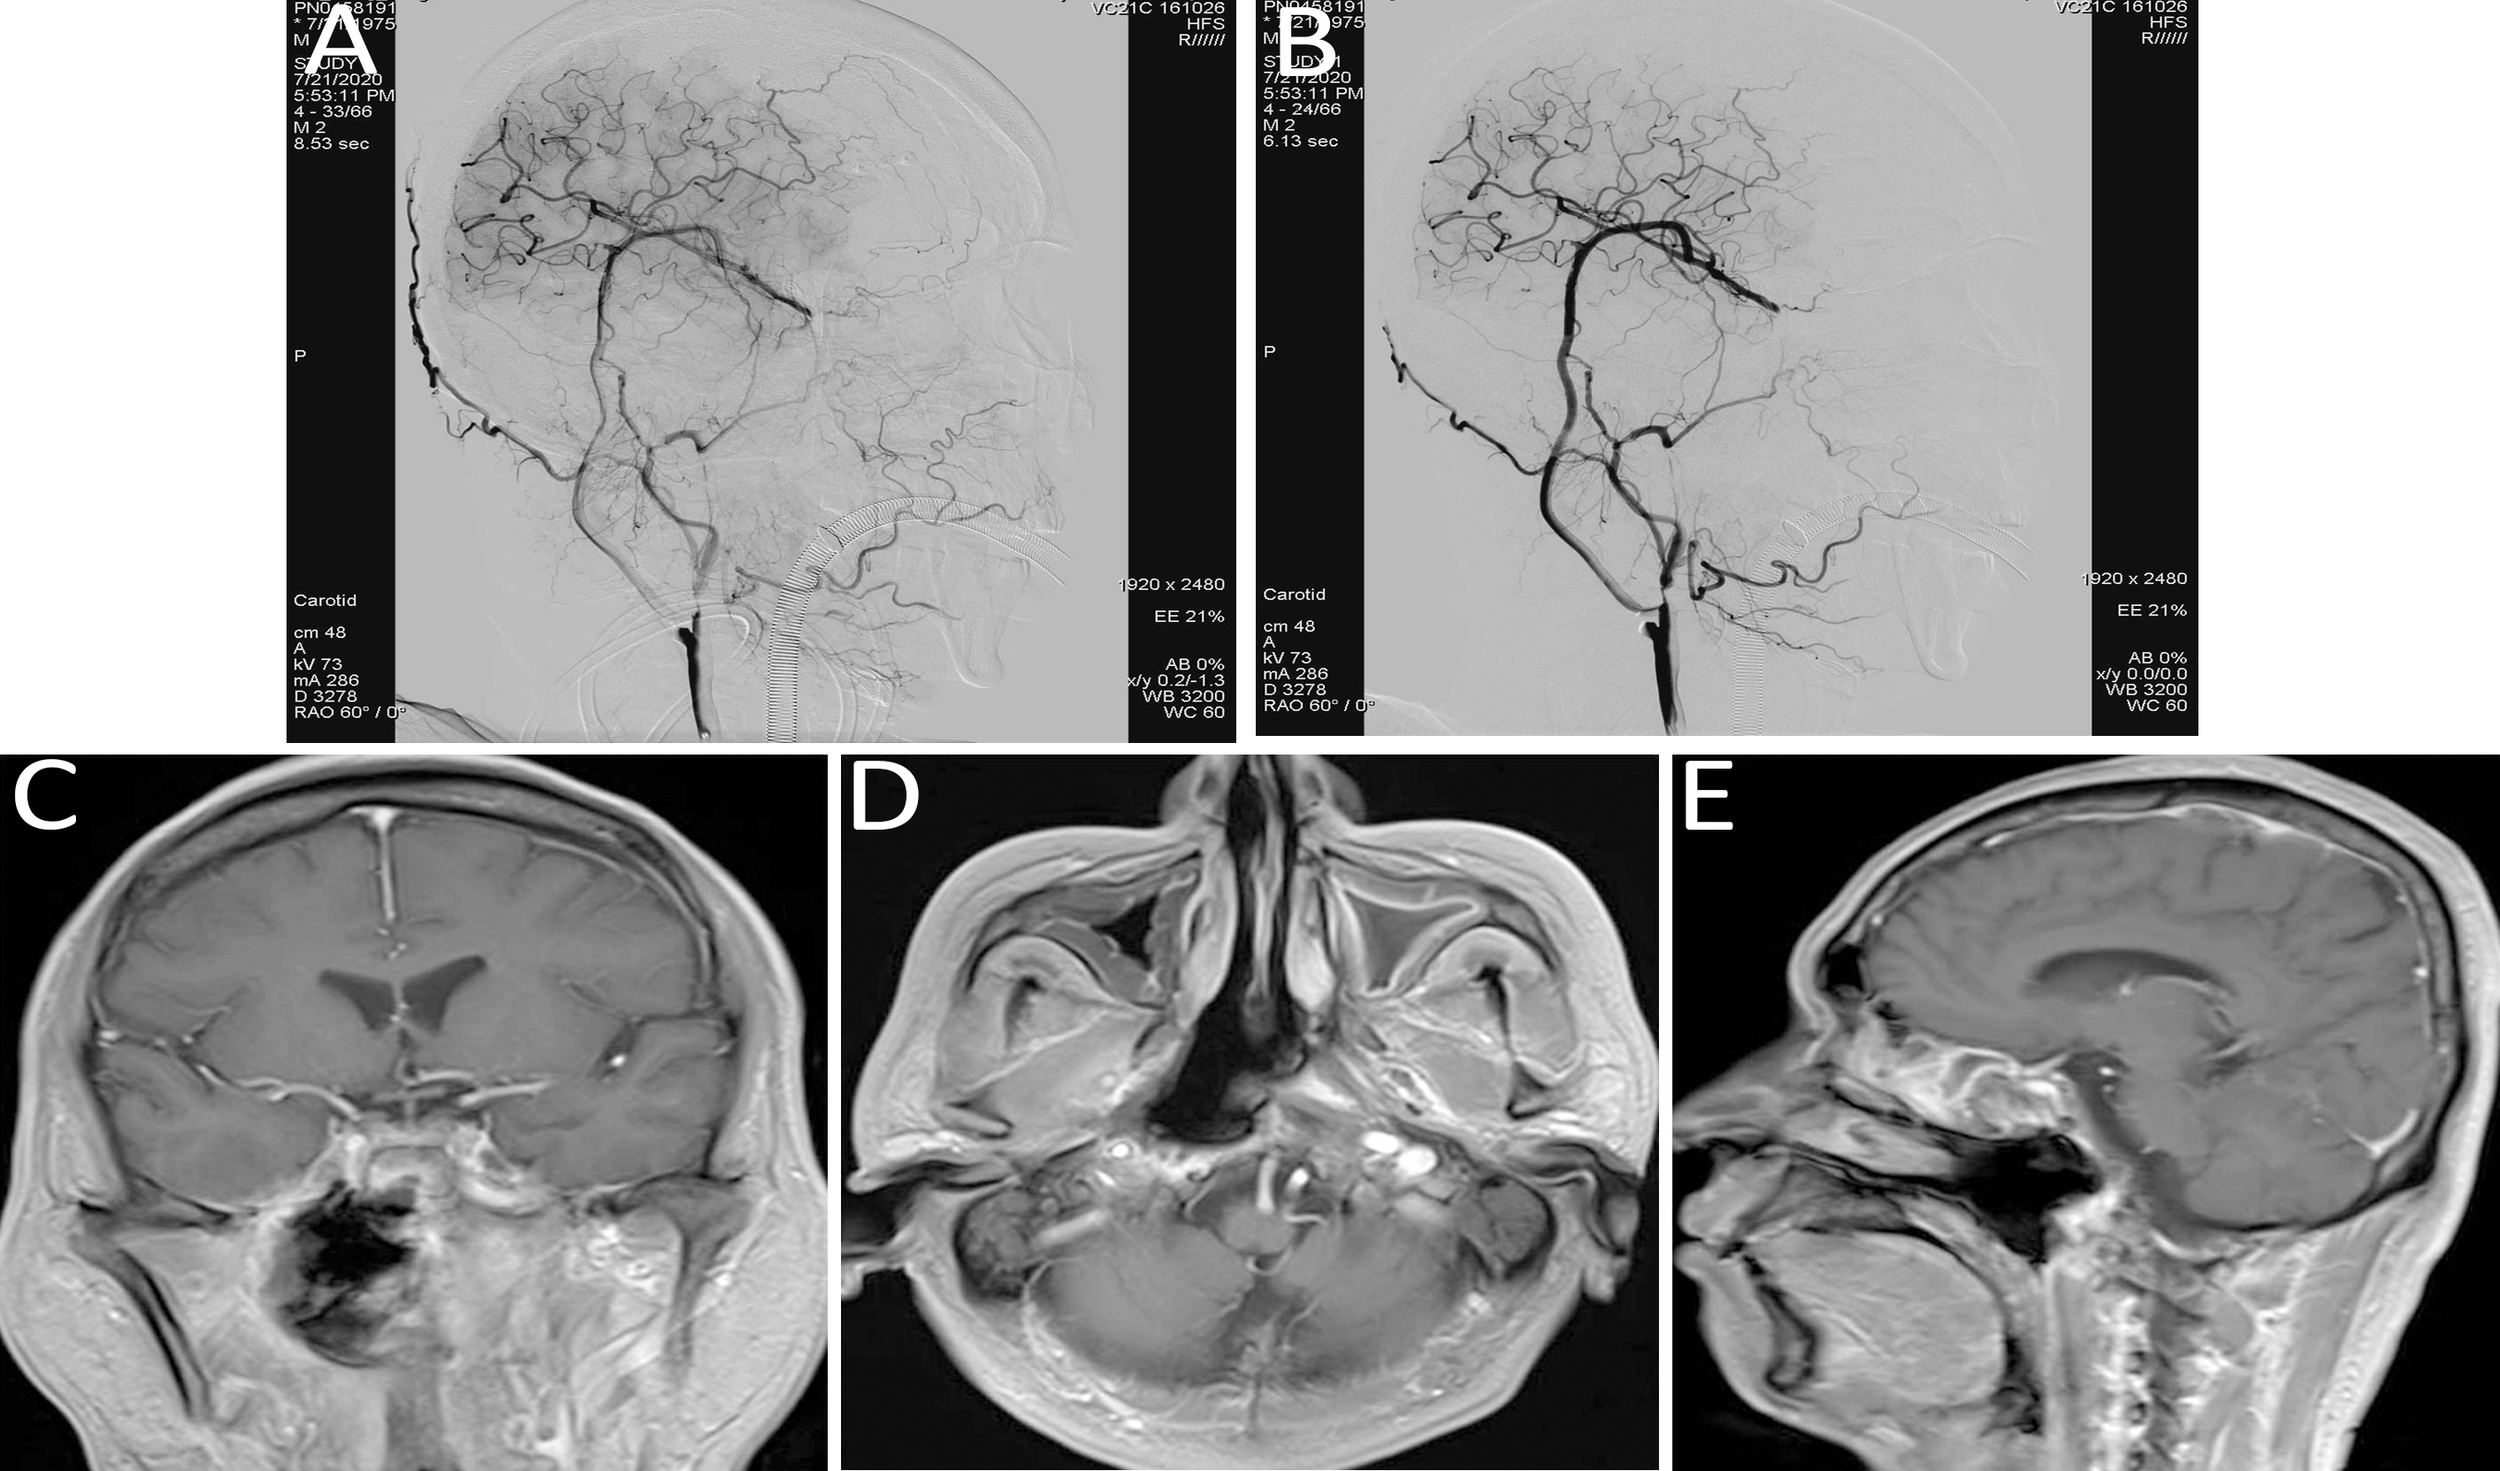

A subsequent surgical procedure was undertaken, involving the creation of a vascular anastomosis from the right external carotid artery to the middle cerebral artery using a grafted radial artery. Concurrently, the cavernous and petrous segments of the right ICA were isolated. Immediate postoperative angiography confirmed patency of the bypass, with sufficient perfusion to the right middle cerebral artery and collateral supply to the ophthalmic artery. No perfusion was observed in the cervical, petrous, and cavernous segments of the right ICA (refer to Figures 4A, B).

Figure 4

(A, B) Immediate post-bypass angiography confirmed patency of the bypass graft, with sufficient perfusion of the right middle cerebral artery and retrograde supply to the ophthalmic artery. No perfusion was observed in the right internal carotid artery at the cervical (C1), petrous (C2), and cavernous (C4) segments. (C–E) Follow-up head MRI demonstrated significant tumor shrinkage and satisfactory local disease control.

Immunotherapy and targeted treatment were continued. Follow-up MRI of the head demonstrated significant tumor shrinkage and favorable local disease control (refer to Figures 4C–E).